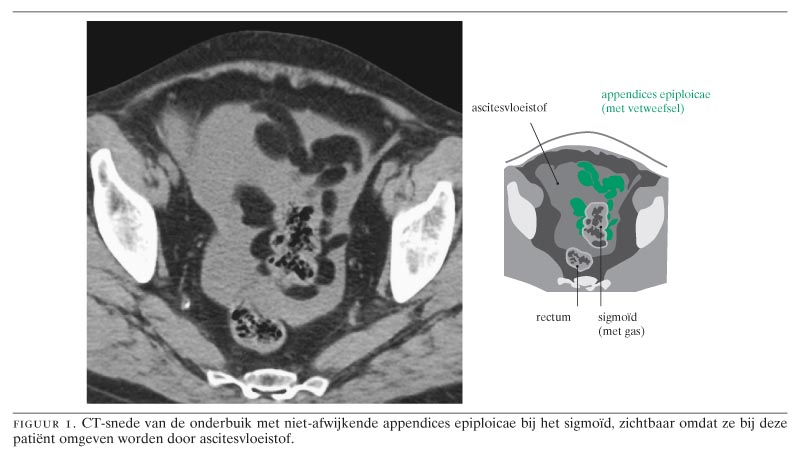

Appendices epiploicae zijn kleine gesteelde vetaanhangels aan de buitenzijde van het colon (figuur 1). De exacte functie van deze appendices is onbekend, maar gedacht wordt aan een rol bij het afdekken en het inperken van een lokale ontsteking, vergelijkbaar met de functie van het omentum, en aan vetopslag als energiereserve.1 Door torsie of knikken van de steel van de appendix of door spontane veneuze trombose kan een appendix epiploica ischemisch worden en infarceren.2 3 Vanwege de daaropvolgende steriele ontsteking is dit ziektebeeld ‘appendicitis epiploica’ genoemd, maar om verwarring te voorkomen met ontsteking van de appendix vermiformis wordt dit vaak vervangen door ‘appendagitis epiploica’.2

De karakteristieke echografische bevinding bij appendagitis epiploica is een 1 tot 4 cm grote intra-abdominaal gelokaliseerde massa van echorijk ontstoken vetweefsel, dat vastzit aan het colon, exact op de plek van de meeste pijnklachten (figuur 2).5 9 Met CT bevestigt men de diagnose door het aantonen van een karakteristieke dense ring in of rondom het ontstoken vetweefsel (figuur 3), hetgeen overeenkomt met oedemateus verdikt visceraal peritoneum rondom de ontstoken appendix epiploica.5 6 9